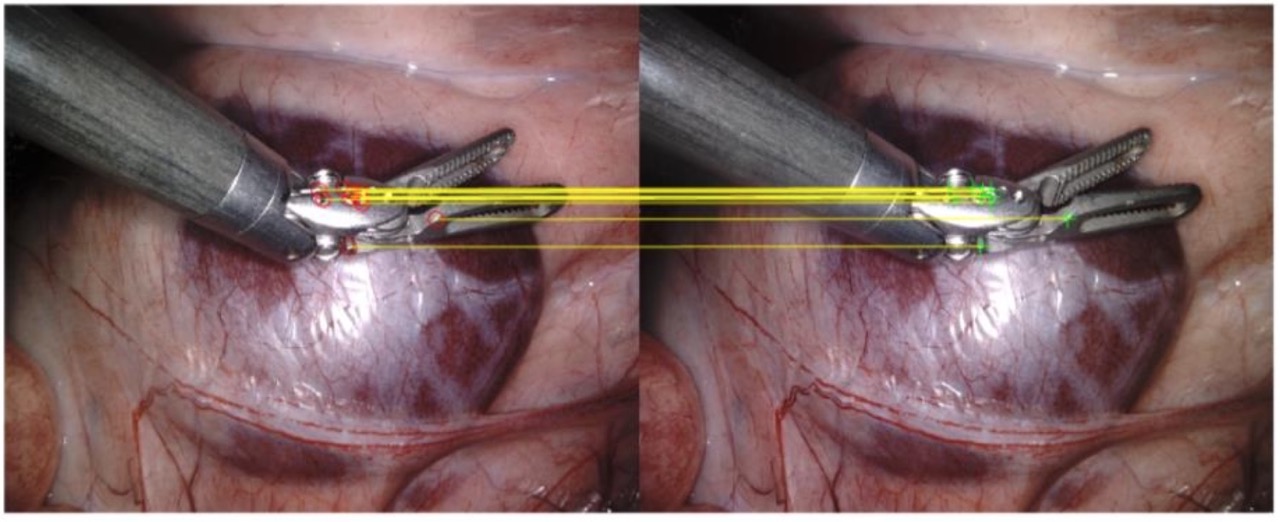

- Stereo Matching: Matched features between stereo views and filtered outliers based on geometric consistency.

- Fundamental Matrix Estimation: Derived the epipolar geometry governing the stereo image pair to constrain valid correspondences.

- Disparity Mapping & Depth Recovery: Generated a dense disparity map and back-projected image points to compute real-world 3D coordinates.

- Quantitative Tool Analysis: Estimated the physical diameter of a surgical tool (∼7.53 mm) directly from the reconstructed point cloud using geometric analysis, achieving 95% accuracy.

✅ Demonstrated the full stereo vision pipeline from calibrated image pairs to quantitative 3D metric extraction in a surgical context — achieving 95% accuracy in depth estimation.